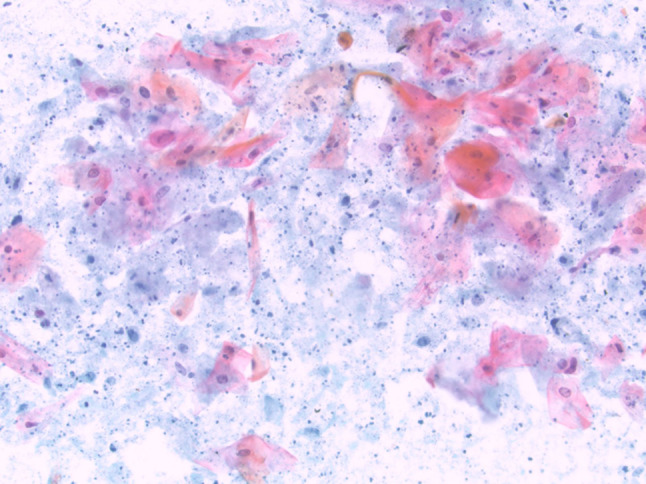

Fig. 13.

(Left) Inflammatory cyst lined by squamous metaplasia (H&E stain, magnification × 40). (Right) FNA of cyst contents from an inflammatory cyst containing scattered atypical metaplastic squamous cells, scant inflammatory cells and numerous orangeophilic crystalloids (Papanicolaou stain, magnification × 60)